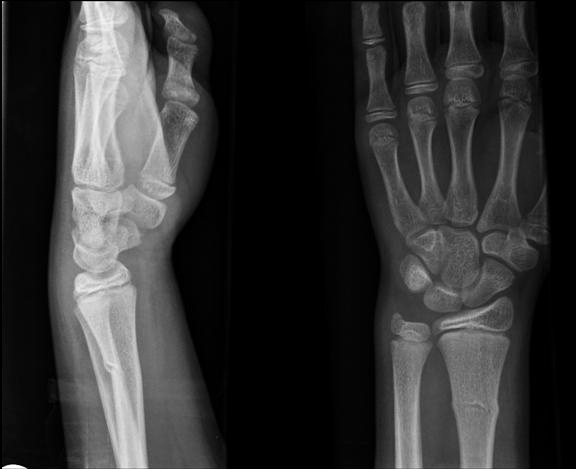

Torus fractures usually occur at the junction of the metaphysis and diaphysis, especially in the distal radius.

Torus fractures are diagnosed with x-ray imaging. This injury is referred to as a torus fracture because of its similarity to the raised band around the base of a classic Greek column when viewed on x-ray.

A Greenstick fracture is an incomplete fracture of long bones that is commonly seen in children. The bone bends and cracks but does not break into pieces, largely due to the softness and flexibility of bones in children.

These fractures occur when the bone is bent and there is failure on the tensile (convex) side of the bone. This is different than in torus fractures where the concave side buckles.

X-ray imaging will show a mid-diaphyseal break, usually with angulation and disruption of the cortical bone on the side of the fracture.